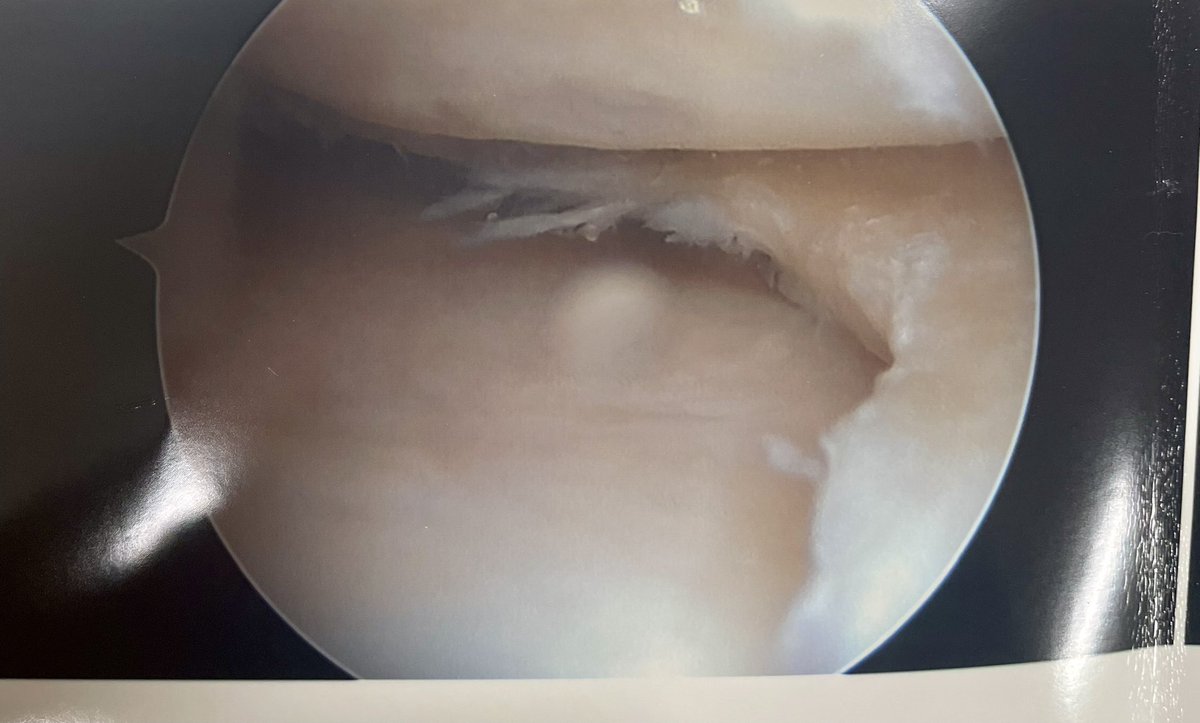

10 week old injury in a 40-year old, biker

Normal gait, able to straight leg raise, knee flexion 0° - 130° , Clarke’s test positive

#Orthotwitter - would you fix it or leave it ?